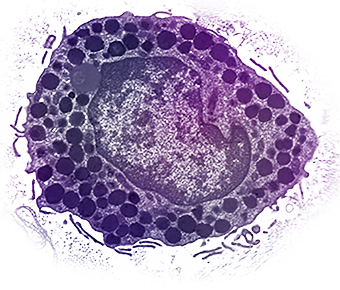

Mast cells are "master regulators" of the immune system. They come from bone marrow and go into all tissues of the body. Each mast cell contains secretory granules (storage sacs), each containing powerful biologically active molecules called mediators. These can be secreted when mast cells are triggered, leading to allergic and inflammatory diseases.